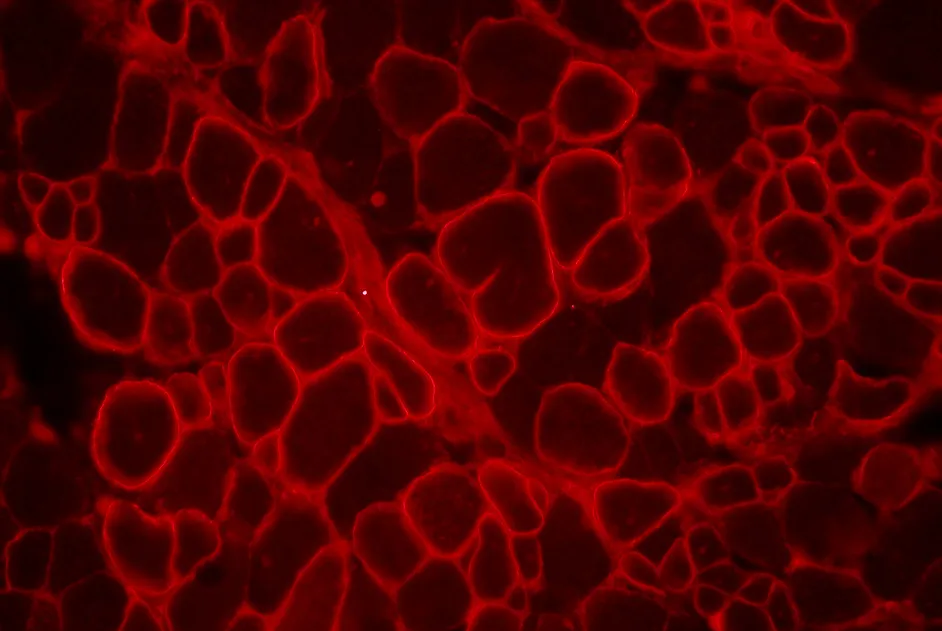

L’étude des deux formes de la protéine DNAJB6 montre que c’est la forme DNAJB6b qui, en désorganisant la structure des fibres musculaires, est responsable de la LGMD1D.